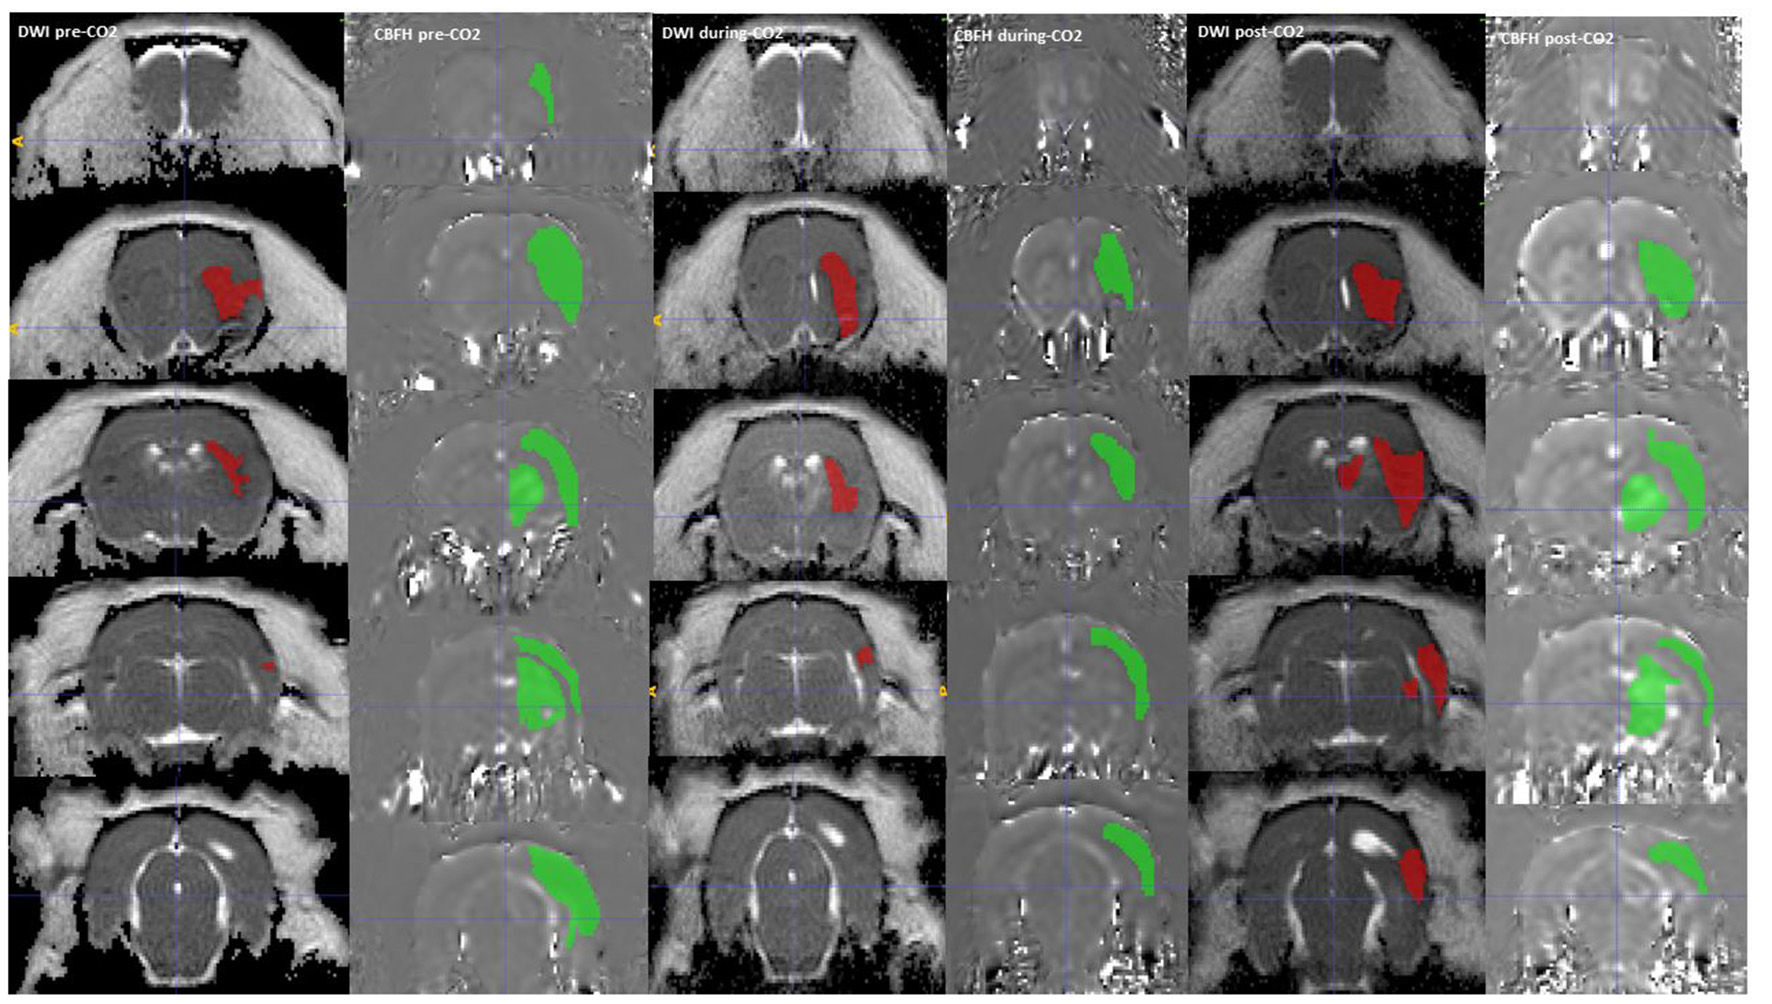

Regions of interest (ROI) segmentation was done with ImageJ and ITK-SNAP software, during which the assessor was blinded to which group the animals were from. Each image was visually inspected, and individual ROIs were manually traced areas with decreased ADC to delineate the ischemic core. ROIs were similarly manually traced around areas with reduced CBF seen on the ASL maps (Figure 2).

In the rats administered CO2 (Groups 1 and 2 combined) the DWI lesion to cerebral hypoperfusion volume ratio (SD) was 0.145 (0.168) at pre-CO2 administration, this increased to 0.708 (0.731) during CO2 administration and subsequently reduced to 0.533 (0.527) post-CO2 administration. In 9 out of 10 rats the volume of the hypoperfused tissue decreased when CO2 was administered but this decrease reversed when the CO2 was discontinued (Figure 3). The mean decrease in CBF hypoperfusion was 0.051 (0.094) for all rats with CO2, 0.079 (0.412) for rats breathing room air + 12% CO2 and 0.0094 (0.141) for rats breathing room air + 6% CO2. Only administration of room air + 12% CO2 decreased the volume of CBF hypoperfusion significantly when compared to the control group (95%CI: 0.034–0.133, p = 0.004) (Table 2). Rat 4 from group 1 did not have a reduction in CBF hypoperfusion with administration of CO2, this is likely due to the large infarct size which involved the hypothalamic region, which caused hyperthermia throughout the experiment (Supplementary Figure 1).

Figure 3

A DWI (Green) and CBF hypoperfusion, CBFH (Red) region of interest drawn onto the corresponding MRI sequences, showing a reduction in CBF hypoperfusion volume with administration of CO2. The CBF hypoperfusion volume reverses and increases with stoppage of CO2.